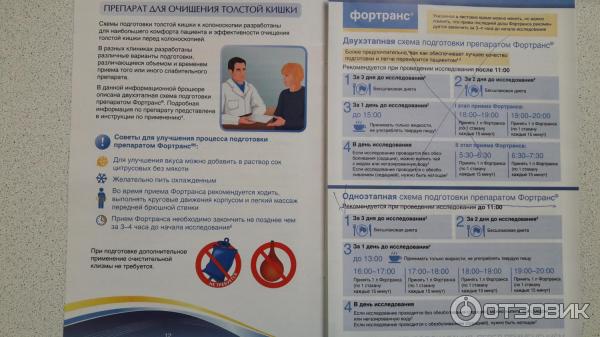

Подготовка к ирригоскопии: необходимые препараты